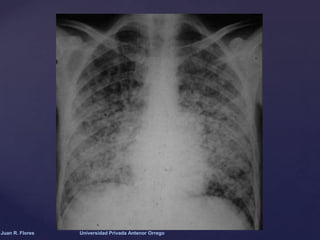

Espectro radiológico de la

infección por Aspergillus

DATOS

RADIOLOGICOS

Colonizante

Invasiva

Alérgica

•Masa sólida, redonda u oval

•Localizada en los lóbulos superiores, adyacente a la

pleura, y separada de la pared de la cavidad por un

espacio aéreo

•Forma y tamaño variable.

•Consolidaciones lobulares, segmentarias o

subsegmentarias, habitualmente múltiples

•Bronquiectasias en fases iniciales

•Opacidades tubulares multifocales relacionadas

con áreas de atelectasia e impactación mucoide.